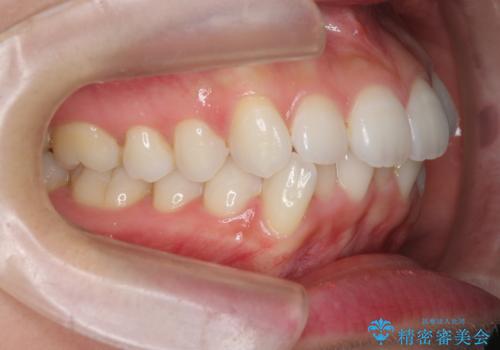

通常口元の突出感の改善を行うには小臼歯の4本抜歯が検討されますが、歯のガタ付きが下顎前歯に限定していることから

下顎前歯を1本だけ抜去を行い、上顎の歯は可及的にマイクロインプラントを用いた後方移動を行い口元の印象の改善を計画することとなりました。

マイクロインプラントを用いてしっかりと後方移動を行ったことで前歯の角度は改善され、口元もすっきりと仕上げることができました。